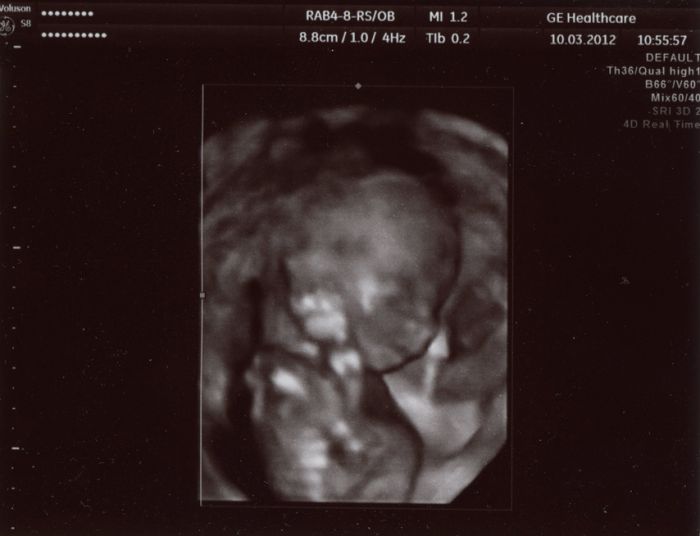

Ahoj holky :-) Až teď píšu, protože jsem po UZ hned jeli pryč na víkend. Takže hlásím, že je vše v pořádku. Miminko má od hlavičky po zadeček 15cm, mrskalo se tam a pořád se šťouralo v oušku nebo v očích. Dr. si nejdřív myslel, že je to kluk, ale pak znejistěl, neboť tam nic neviděl, nebo spíš to nebylo úplně jasně vidět. Každopádně jasnej pindík tam sice vidět nebyl, ale nechtěl nám s jistotou potrvzovat holčičku, co kdyby tam dole ještě něco narostlo??!! ;-) Takže opět nevím nic, ale my se přikláníme k tomu, že to bude holčička ;-)

Tady je pár foteček. Video dostanu za 2 týdny až tam půjdu na kontrolu. Ten jeho přístroj mu to nedovede hned zpracovat, tak nám to video nemohl hned dát.

Tedy Blanko, to jsou fakt nááádherné fotečky!

Fakt krásně vyfocené....Tak to moc gratuluji!

Člověče,nevím proč, ale také mi to miminko přijde jako holčička